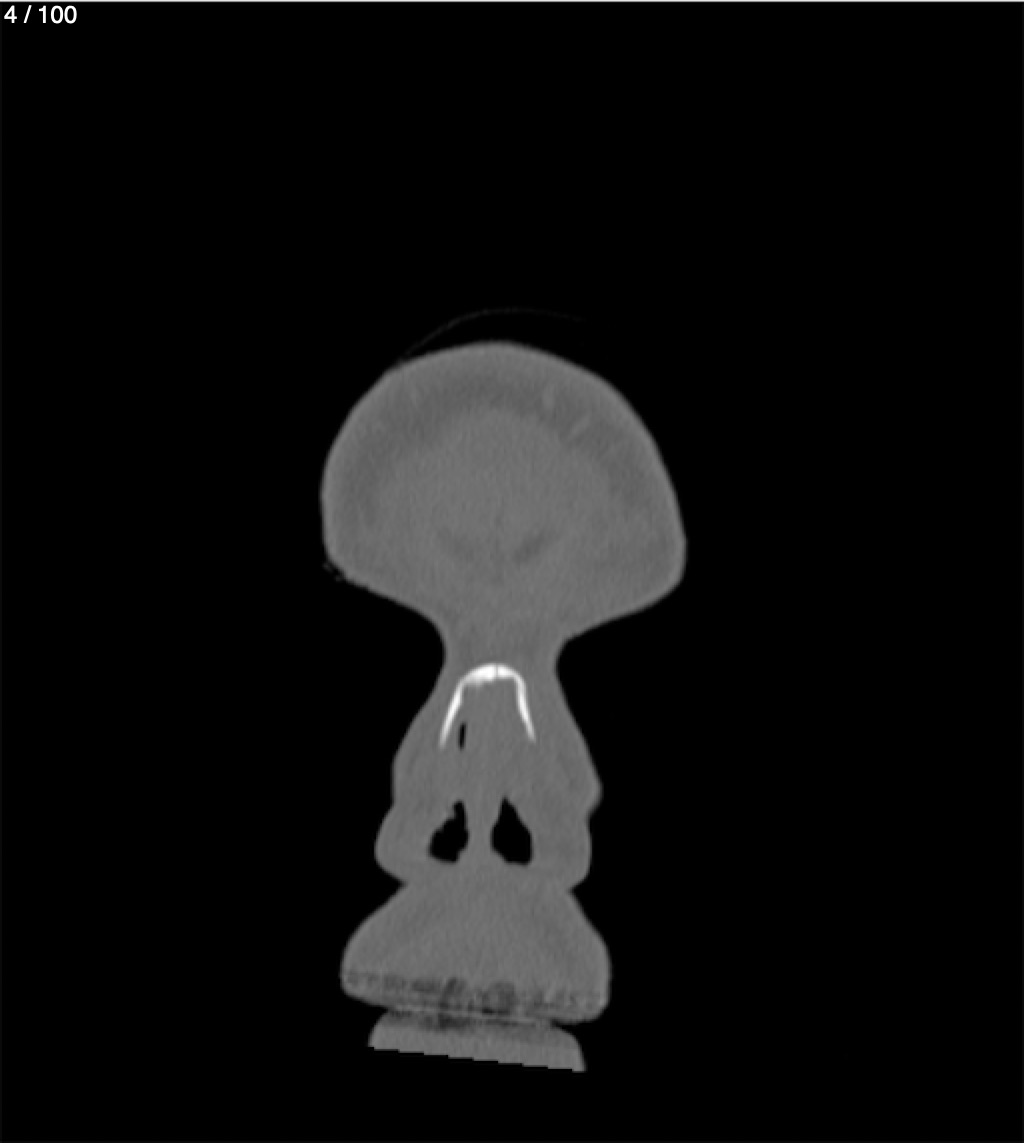

Reybet Garcia Fuentes 30A - T.C Craneo